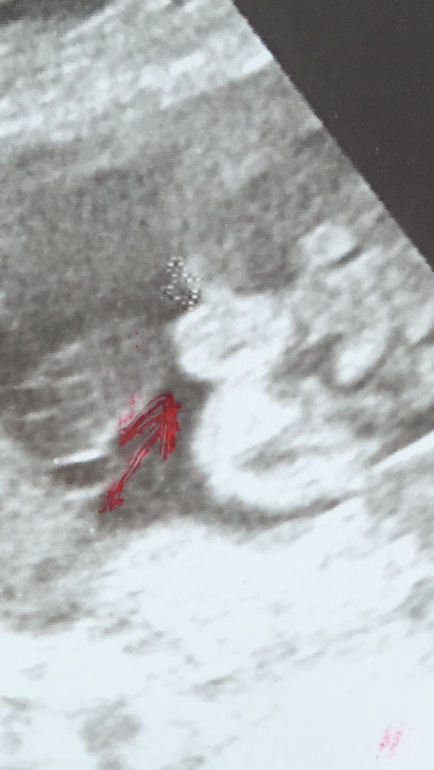

Кто на УЗИ? Мнения врачей разошлись, последнее предположение мальчишка))

Мне кажется мальчик, у моего первого сына было так же. Врач сказала яички)